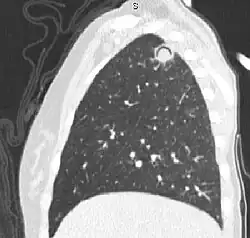

| The arrows denote an ill-defined nodular opacity in medial aspect of right upper lobe with ill-defined rim of lucency surrounding it | |

| Differential diagnosis | Aspergilloma |

In radiology, the air crescent sign (also called the Monad sign[1]) is a finding on chest radiograph and computed tomography that is crescenteric and radiolucent, due to a lung cavity that is filled with air and has a round radiopaque mass.[2] Classically, it is due to an aspergilloma, a form of aspergillosis, that occurs when the fungus Aspergillus grows in a cavity in the lung.[3]